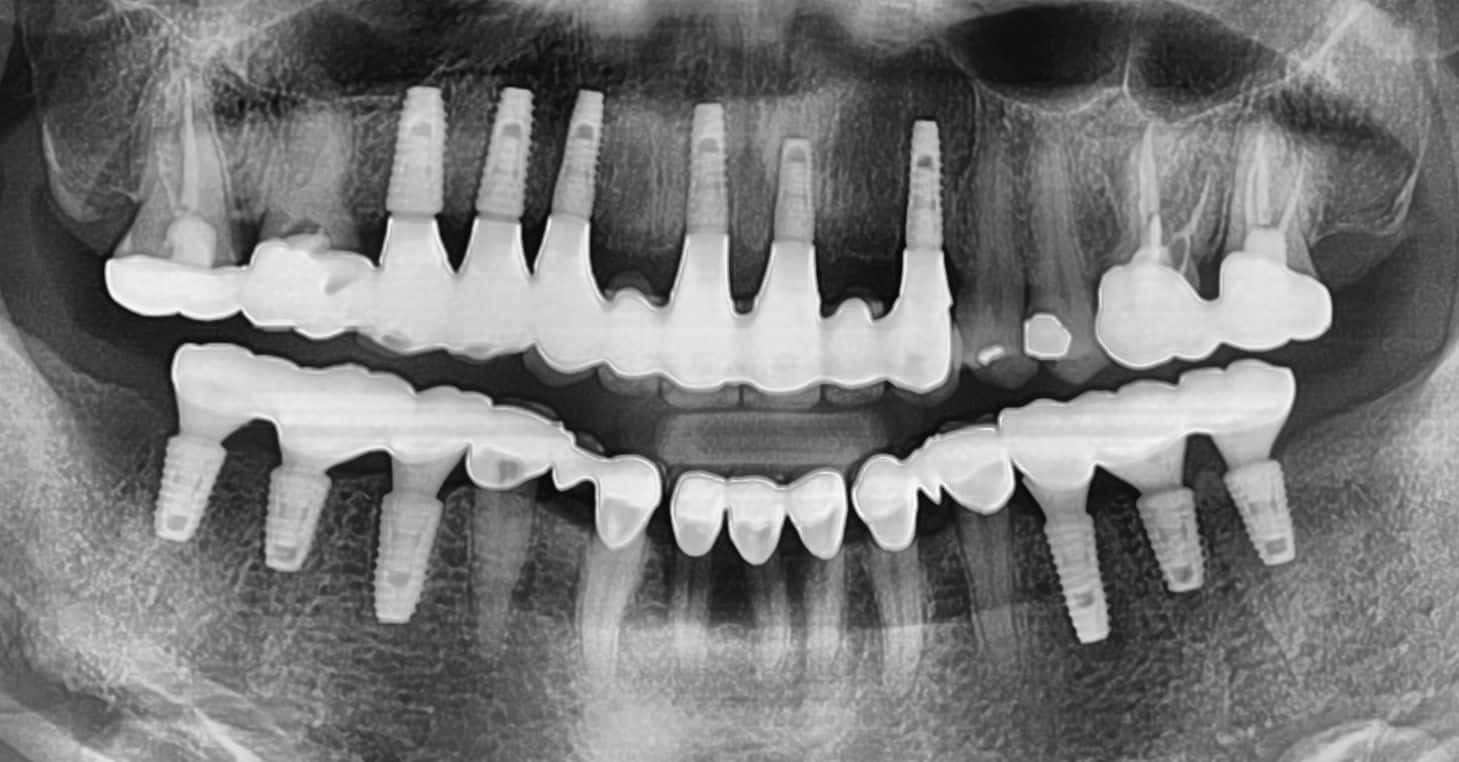

This patient was suffering from significant pain in her upper jaw due to infection. I performed extensive bone grafting procedures, including a sinus lift, to prepare the site for implant placement. Five dental implants were successfully placed, and the patient recovered without any complications.